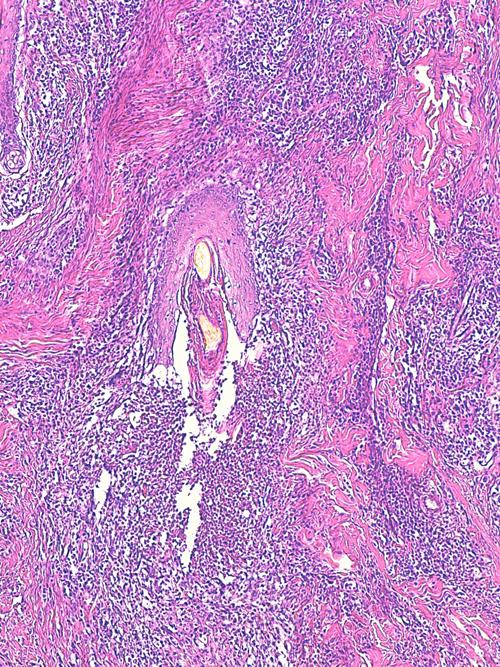

Photo 13 (Hémalun Eosine X 100) peau velue : dans le derme, de nombreux

follicules pileux sont rompus doannant naissance à des foyers furonculeux.

Légendes de la Photo 13 :

- Étoiles noires : infiltrat inflammatoire dermique et effondrant le follicule pileux

- Double flèche pointillée noire : gaine épithéliale externe du follicule pileux

- Ronds marrons : tige pilaire

- Flèches jaunes : rupture du follicule pileux (furonculose)